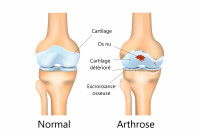

Chez un chien comme chez un humain, la mobilité des membres est assurée par les articulations, qui joignent les os entre eux. Ces dernières contiennent du cartilage, un tissu souple et élastique qui joue le rôle d'amortisseur lors des mouvements pour limiter les chocs et les frottements.

Comme les autres tissus de l'organisme, le cartilage est en capacité de se restaurer lorsqu'il est endommagé. Toutefois, contrairement aux os par exemple, il se régénère peu et cicatrise difficilement. Or, dans le même temps, il est soumis à toutes sortes de tensions. L'équilibre qui lui permet de se maintenir en bon état est donc fragile.

Or, il arrive qu'un déséquilibre se produise : soit les contraintes qui s'exercent sur l'articulation sont trop importantes (par exemple à la suite d'une blessure), soit le cartilage est fragilisé et ne parvient plus à gérer les contraintes habituelles qu'il subit (souvent tout simplement du fait du vieillissement). Dans un cas comme dans l'autre, les cellules chargées de la restauration du cartilage s'emballent et provoquent une inflammation, qui contribue à sa dégradation. S'installe alors un véritable cercle vicieux qui conduit à une destruction progressive du cartilage : c'est ce phénomène que l'on appelle l'arthrose.

De plus, comme il est endommagé, il ne joue plus correctement son rôle d'amortisseur. Des frottements anormaux se produisent alors sur les os de l'articulation lors des mouvements : ces derniers s'abîment progressivement et changent de forme à leur extrémité, ce qui limite l'amplitude des mouvements qu'ils peuvent réaliser. À terme, toute l'articulation finit par être détériorée : il en résulte une perte de mobilité plus ou moins importante du membre atteint.